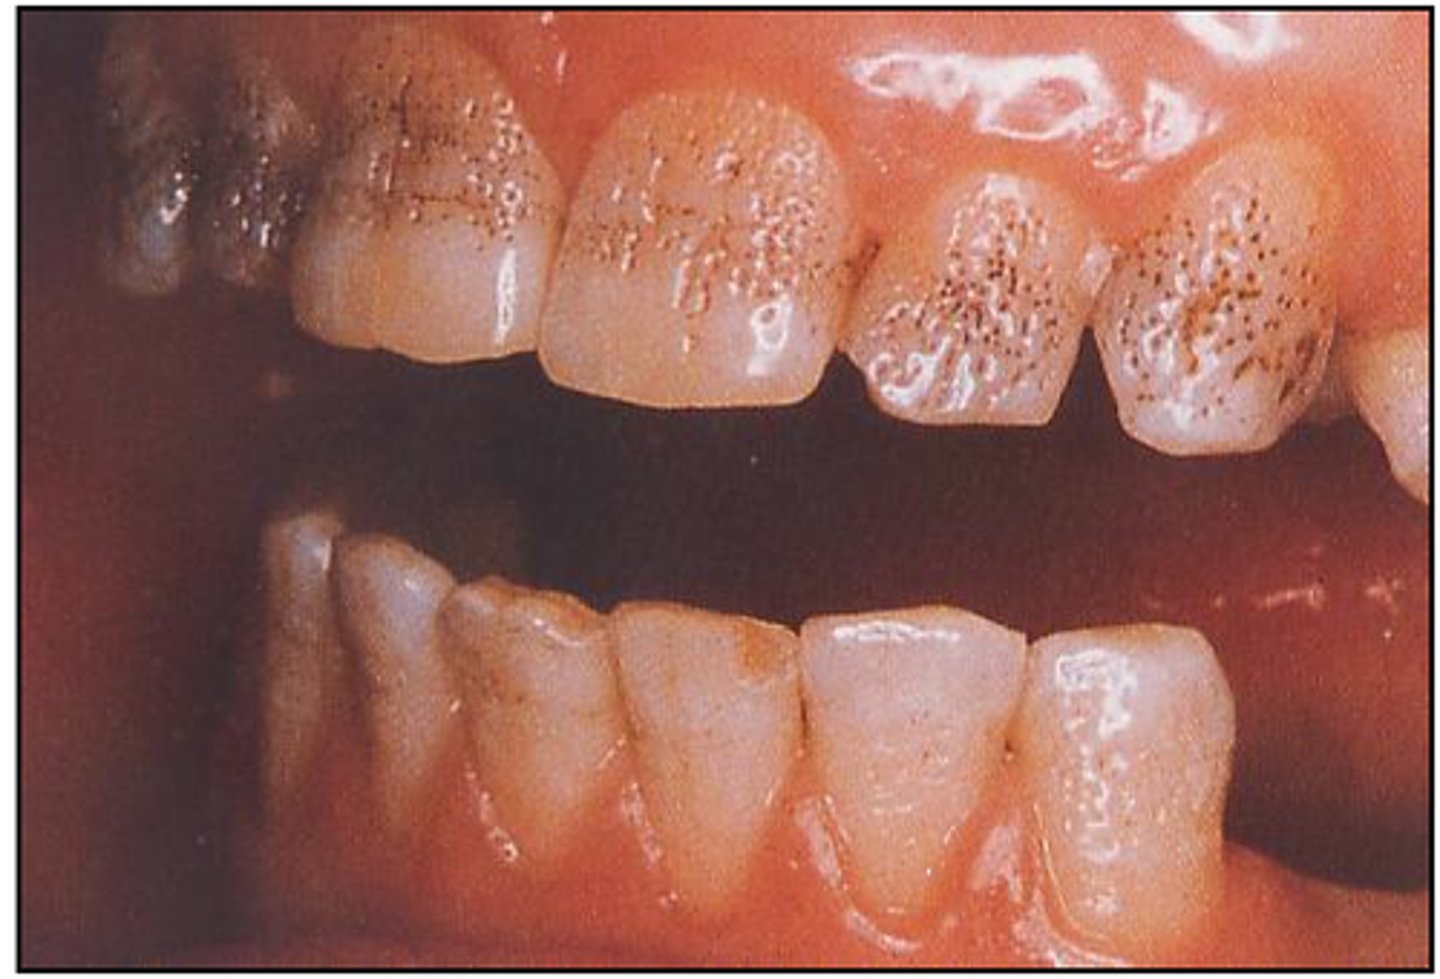

Pt presents, upset with look of with canine and premolar area; spotted (pick up stains), pits and grooves on outer surface of teeth. Likely diagnosis

- hypoplasia

- hyperplasia

- abfraction

- erosion

(on 2024 exam)

hypoplasia; consider that fact it is localized, likely not related to systemic disease